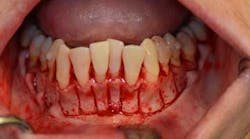

SFOT was used with a high-tech clear aligner to address hard- and soft-tissue deficiencies and severe maxillary and mandibular arch constriction.

A healthy, 57-year-old female presented with a lifelong desire for healthy, straight teeth and a beautiful smile. She had been told numerous times that it was not possible without premolar extractions.

SFOT surgery was performed in the maxillary and mandibular arches with deep buccal corticotomies. Particulate, demineralized, freeze-dried bone allograft and acellular dermal matrix were used to augment the ridges.